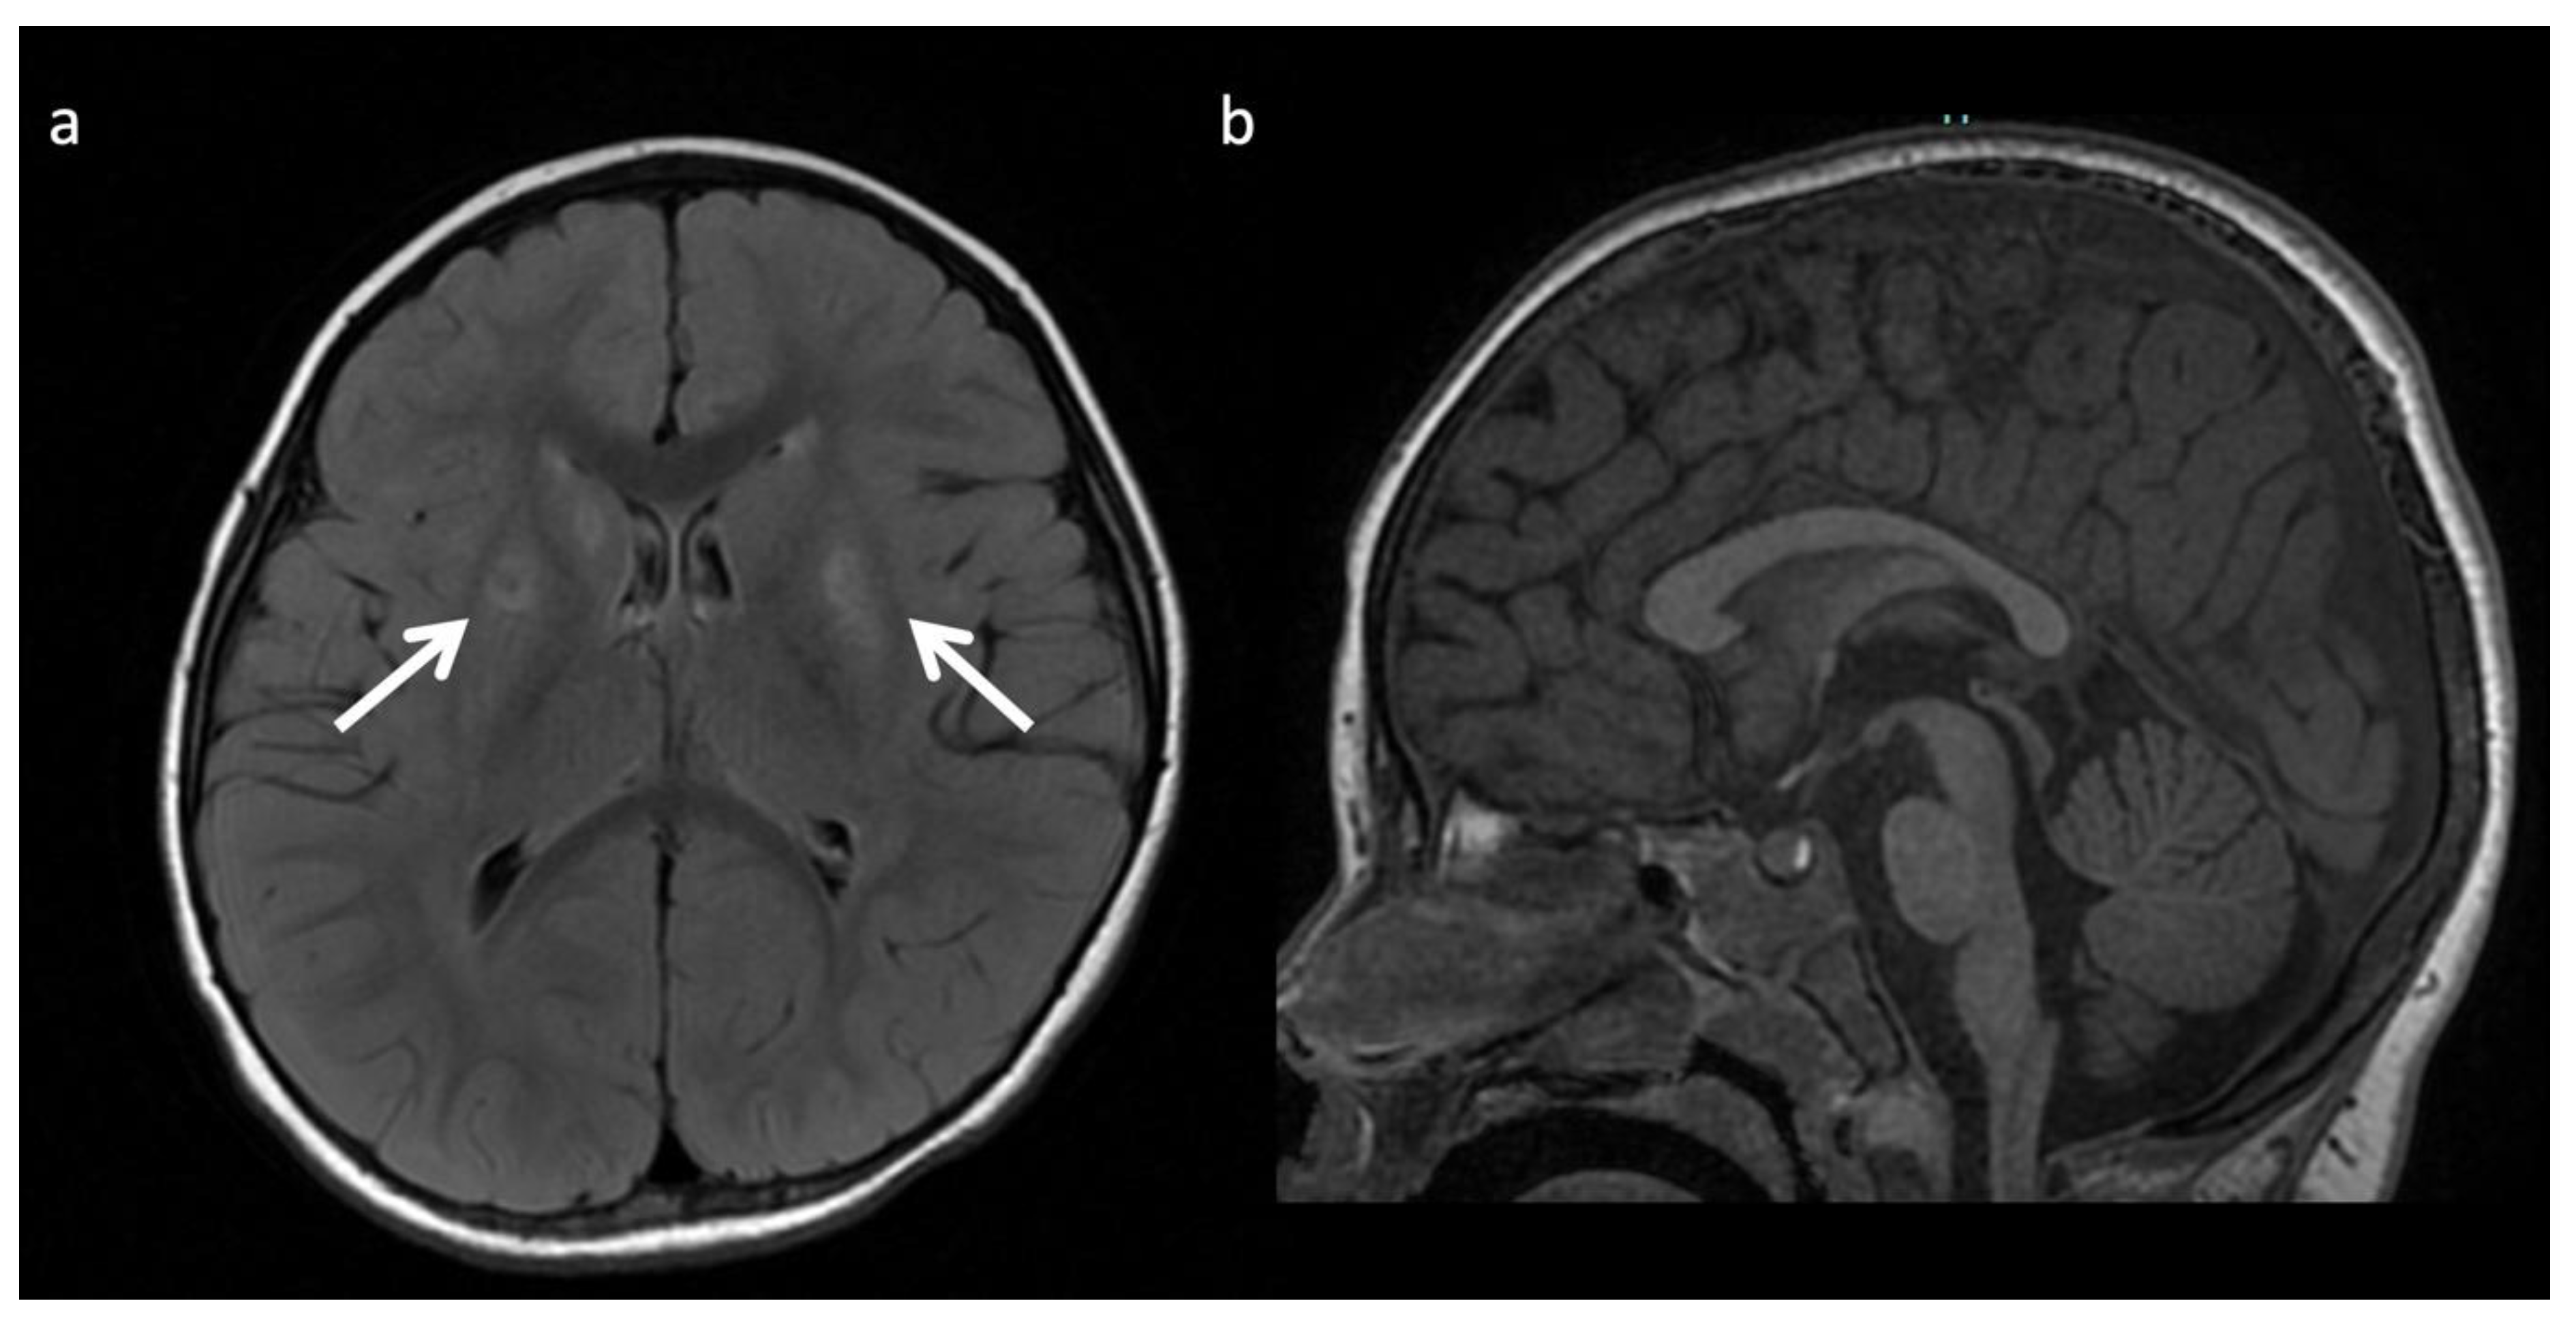

Urea Cycle disorders (Figure 2): Urea cycle disorders (UCD) are caused by defects in the conversion of ammonia to urea, resulting in accumulation of ammonia and glutamine (Gln). Gln is osmotically active, leading to diffuse edema in the cerebral cortex and subcortical white matter when in large concentrations. Brain MR findings characteristic to UCD-related hyperammonemia include a central pattern of edema involving the peri-rolandic, peri-insular, and basal ganglia regions, often sparing the thalami, which helps distinguish it from HIE [3,7,8].

Figure 2.

Example of hyperammonemia induced brain injury, as can be seen with urea cycle disorders. (a) Axial T2 and (b) axial diffusion weighted imaging (DWI) at the level of the basal ganglia show the typical pattern of hyperammonemic central brain involvement with perisylvian, periinsular, and basal ganglia signal hyperintensity consistent with mixed vasogenic and cytotoxic (white arrows, b) edema. (c) Single voxel (SV) short TE MRS demonstrates increased glutamine and glutamate (glx) with overlapping peaks at 2–2.5 ppm (2.4 ppm peak corresponds to elevated glutamine) and an elevated peak at 3.8 ppm consistent with glx associated alpha protons (glx-a). Lac and Cr are also elevated while Cho is depressed.

MRS shows elevated Glu/Gln peaks between 2 and 2.5 ppm during times of hyperammonemia, and a lactate doublet at 1.3 ppm when mitochondrial function fails to meet metabolic demand [3]. Glu/Gln resonances overlap at 1.5T but are more separable at 3T due to chemical shift dispersion; the peak centered at 2.4 corresponds more to glutamine [16]. There is also a commonly overlooked glx peak produced by alpha protons at 3.75 ppm. MI and Cho are usually reduced in chronic hyperammonemia, findings that can be highly suggestive of an underlying UCD in the correct clinical context [6,17].